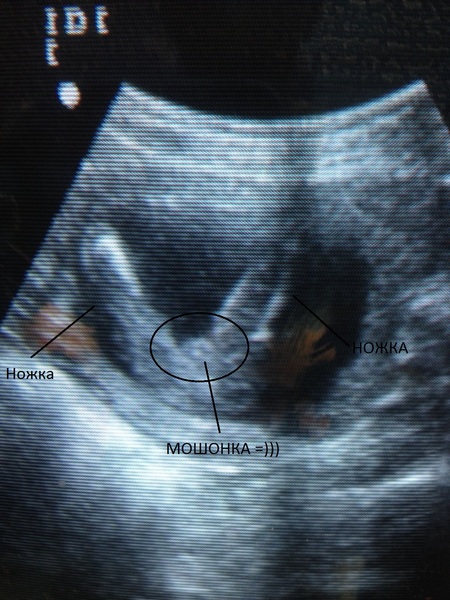

Kaip atrodo pilvukai per aštuonioliktą savaitę? Visiems skirtinga. Kai kurioms motinoms atrodė, kad jos praryja kamuolį, o kitoms pilvas driekėsi iš viršaus į apačią. Viskas gerai. Kartais jie net pagal savo pilvo formą bando atspėti, ar gims mergaitė, ar berniukas.Ir vis dėlto tik ultragarso specialistas gali jums užtikrintai pasakyti, ar šią savaitę jums paskirtas toks tyrimas, ir vaikas nori pasidalyti paslaptimi.

Ultragarsinės nuotraukos